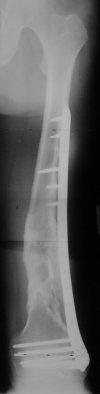

I presented a series of ~25 such cases at EuroTrauma'2004. Many cases were discussed here. I attach am example. Look also recent cases at http://www.hwbf.org/hwb/conf/alex58/scfx.htm,

http://www.hwbf.org/hwb/conf/alex63/alex63.htm

THX, initial images are

1,

2.

At that moment we had in stock only the 10 mm solid nails so of course there was no idea about early weight bearing. But it was quite enough for early knee ROM excersises (see attached). Two locking screws through the distal block provided that.